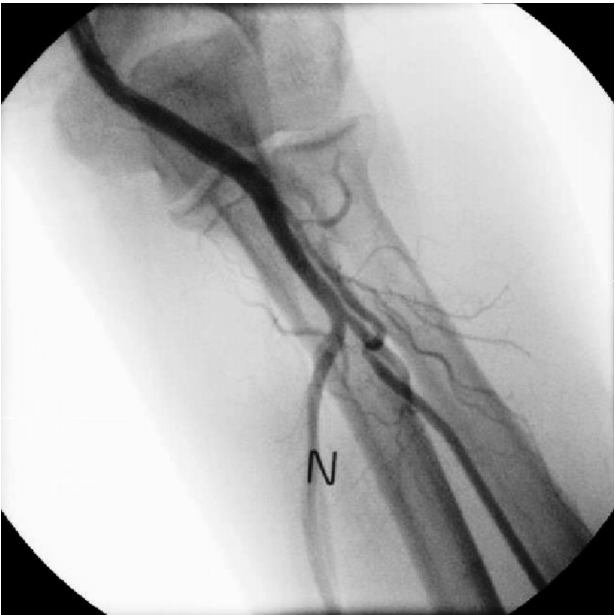

The patient underwent coronary angiography via the left radial route with a 6 French (Fr) sheath (Terumo Corp., Tokyo, Japan) inserted using standard techniques. The left radial angiography showed a minor degree radial artery spasm (Fig. 1A). After injecting 200 μg of nitroglycerin via the radial artery, coronary angiography was successfully performed with 5 Fr JL4 and JR4 diagnostic catheters. The distal LCX lesion was similar to the lesion revealed by the coronary CT scan (Fig. 2A); therefore, PCI was deemed the best treatment option. During insertion of a 6 Fr extra back-up (EBU) guiding catheter (Medtronic, Dublin, Ireland) over a 0.035-inch standard guidewire, the catheter encountered resistance and the patient complained of pain in the left forearm. After removing the 6 Fr EBU guiding catheter, radial angiography was performed by injecting diluted contrast agent through the side port of the sheath. The contrast agent revealed perforation and extravasation of contrast agent into the surrounding tissue (Fig. 1B). A 5 Fr EBU was able to pass the perforated segment over the remaining 0.035-inch standard guidewire. PCI was performed successfully with balloon angioplasty and a 2.75 X 18-mm stent (Resolute integrity, Medtronic, Dublin, Ireland) (Fig. 2B). After removing the guiding catheter, radial angiography was performed via the sheath’s side port. The procedure showed that the perforation was sealed and that there was no contrast agent extravasation (Fig. 3).

Baseline radial angiogram showing a minor degree spasm (arrow) (A). Perforation of the radial artery and extravasation of contrast agent into the surrounding tissue (arrowheads) (B). N, nitroglycerin.